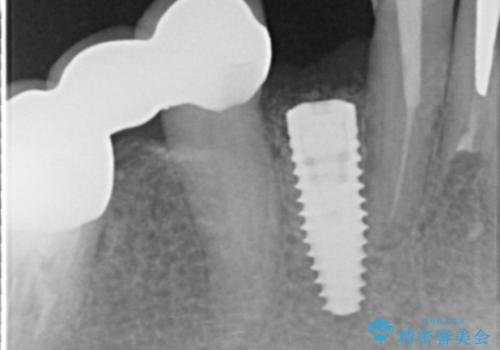

X線写真および歯周組織検査より、歯の破折 周囲骨の高度な吸収が認められました。

抜歯後、インプラントによる審美・機能改善を希望されたのでインプラント埋入に先立ち吸収した骨の再生を計画します。

- 50万円(ストローマンインプラント・骨造成・ジルコニアカスタムアバットメント・ジルコニアクラウン)費用は治療当時の料金となります

歯を失う原因が虫歯や根尖病変などはなく、歯周病や歯の破折等周囲の骨を吸収する原因の場合はインプラント治療を行うに先立ち骨の造成が必要なことがあります。